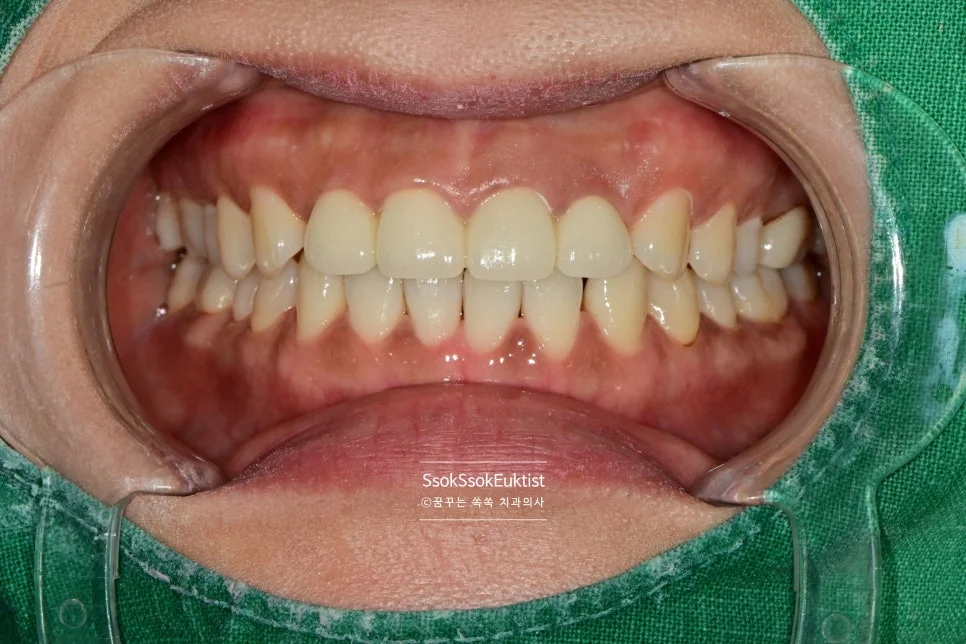

수면 스케일링 전후 비교 구강 사진

수면 스케일링 전후 비교

수면 스케일링 후 깨끗한 치아

After — 수면 스케일링 후

왼쪽 위 치경부 우식을 레진으로 예쁘게 치료한 후 스케일링도 시행하였는데요. 비교적 깨끗하고 건강해진 모습이 보입니다~^^